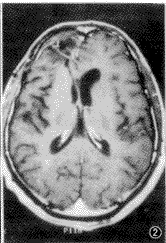

试验组术后反应性增强的发生率为74.6%(417/559)(图1~3),最早可出现在术后24h之内,其持续时间长短不一,最短者持续2个月,最长者可持续至术后9个月,平均6个月左右消失。在术后8~25d时增强最明显。术后残存肿瘤增强的发生率为24.2%(135/559)(图4~6)。有7例术后无增强,其中5例在术后24h之内行MR检查,2例分别在术后41 d和45 d时行MR检查。对照组术后反应性增强的发生率为85.9%(108/126)。因对照组术前无增强,其术后残存的发生率未统计。术后反应性增强与术后残存增强的影像学表现特点见表1。

图1~3 患者 男,35岁。左额星形胶质细胞瘤术后第8d,术区周边有不规则环形增强,边缘比较清楚,厚度均匀,<3 mm(图1);术后3个月,术区明显缩小,原术区边缘增强已不明确,占位效应消失(图2);术后6个月,术区软化灶形成,原有增强已消失(图3),说明图1的增强为术后反应性增强